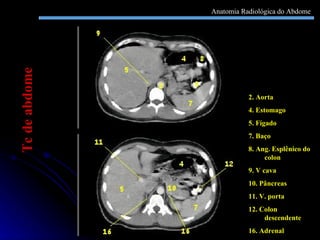

2. Aorta 4. Estomago 5. Fígado 7. Baço 8. Ang. Esplênico do colon 9. V cava 10. Pâncreas 11. V. porta 12. Colon descendente 16. Adrenal Tc de abdome Anatomia Radiológica do Abdome

2. Aorta 4.Estomago 5. Fígado 7. Baço 8. Ang. Esplênico do colon 9. V cava 10. Pâncreas 11. V. porta 12. Colon descendente 16. Adrenal Tc de abdome Anatomia Radiológica do Abdome